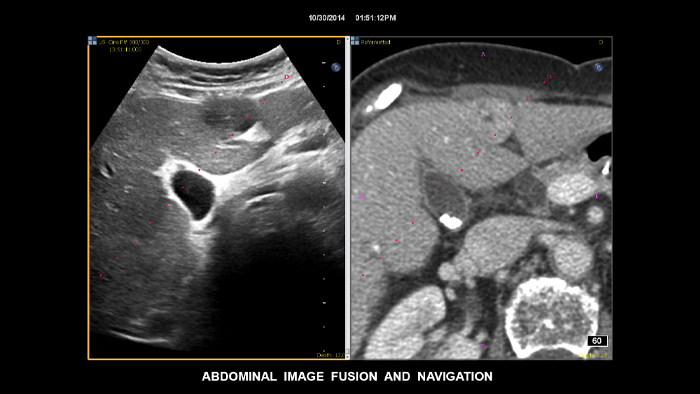

フィリップスのフュージョンとニードルナビゲーション機能を使用して、診断が困難な症例でも信頼性の高い検査の実施をサポートします。合理化されたワークフローにより、ユーザーはCT/MRI/PET画像とリアルタイムの超音波画像を迅速かつ効率的にフュージョンすることが可能です。小さくてアクセスが難しい症例の生検には、ニードルナビゲーションによるガイドも実施することができます²。 腫瘍輪郭マーカーを使用すると、半自動的に3Dのマーカーを生成し、プランニングおよび病変の位置を把握することができます。腫瘍輪郭マーカーを用いることで難易度の高い症例における、手技の向上に貢献します。